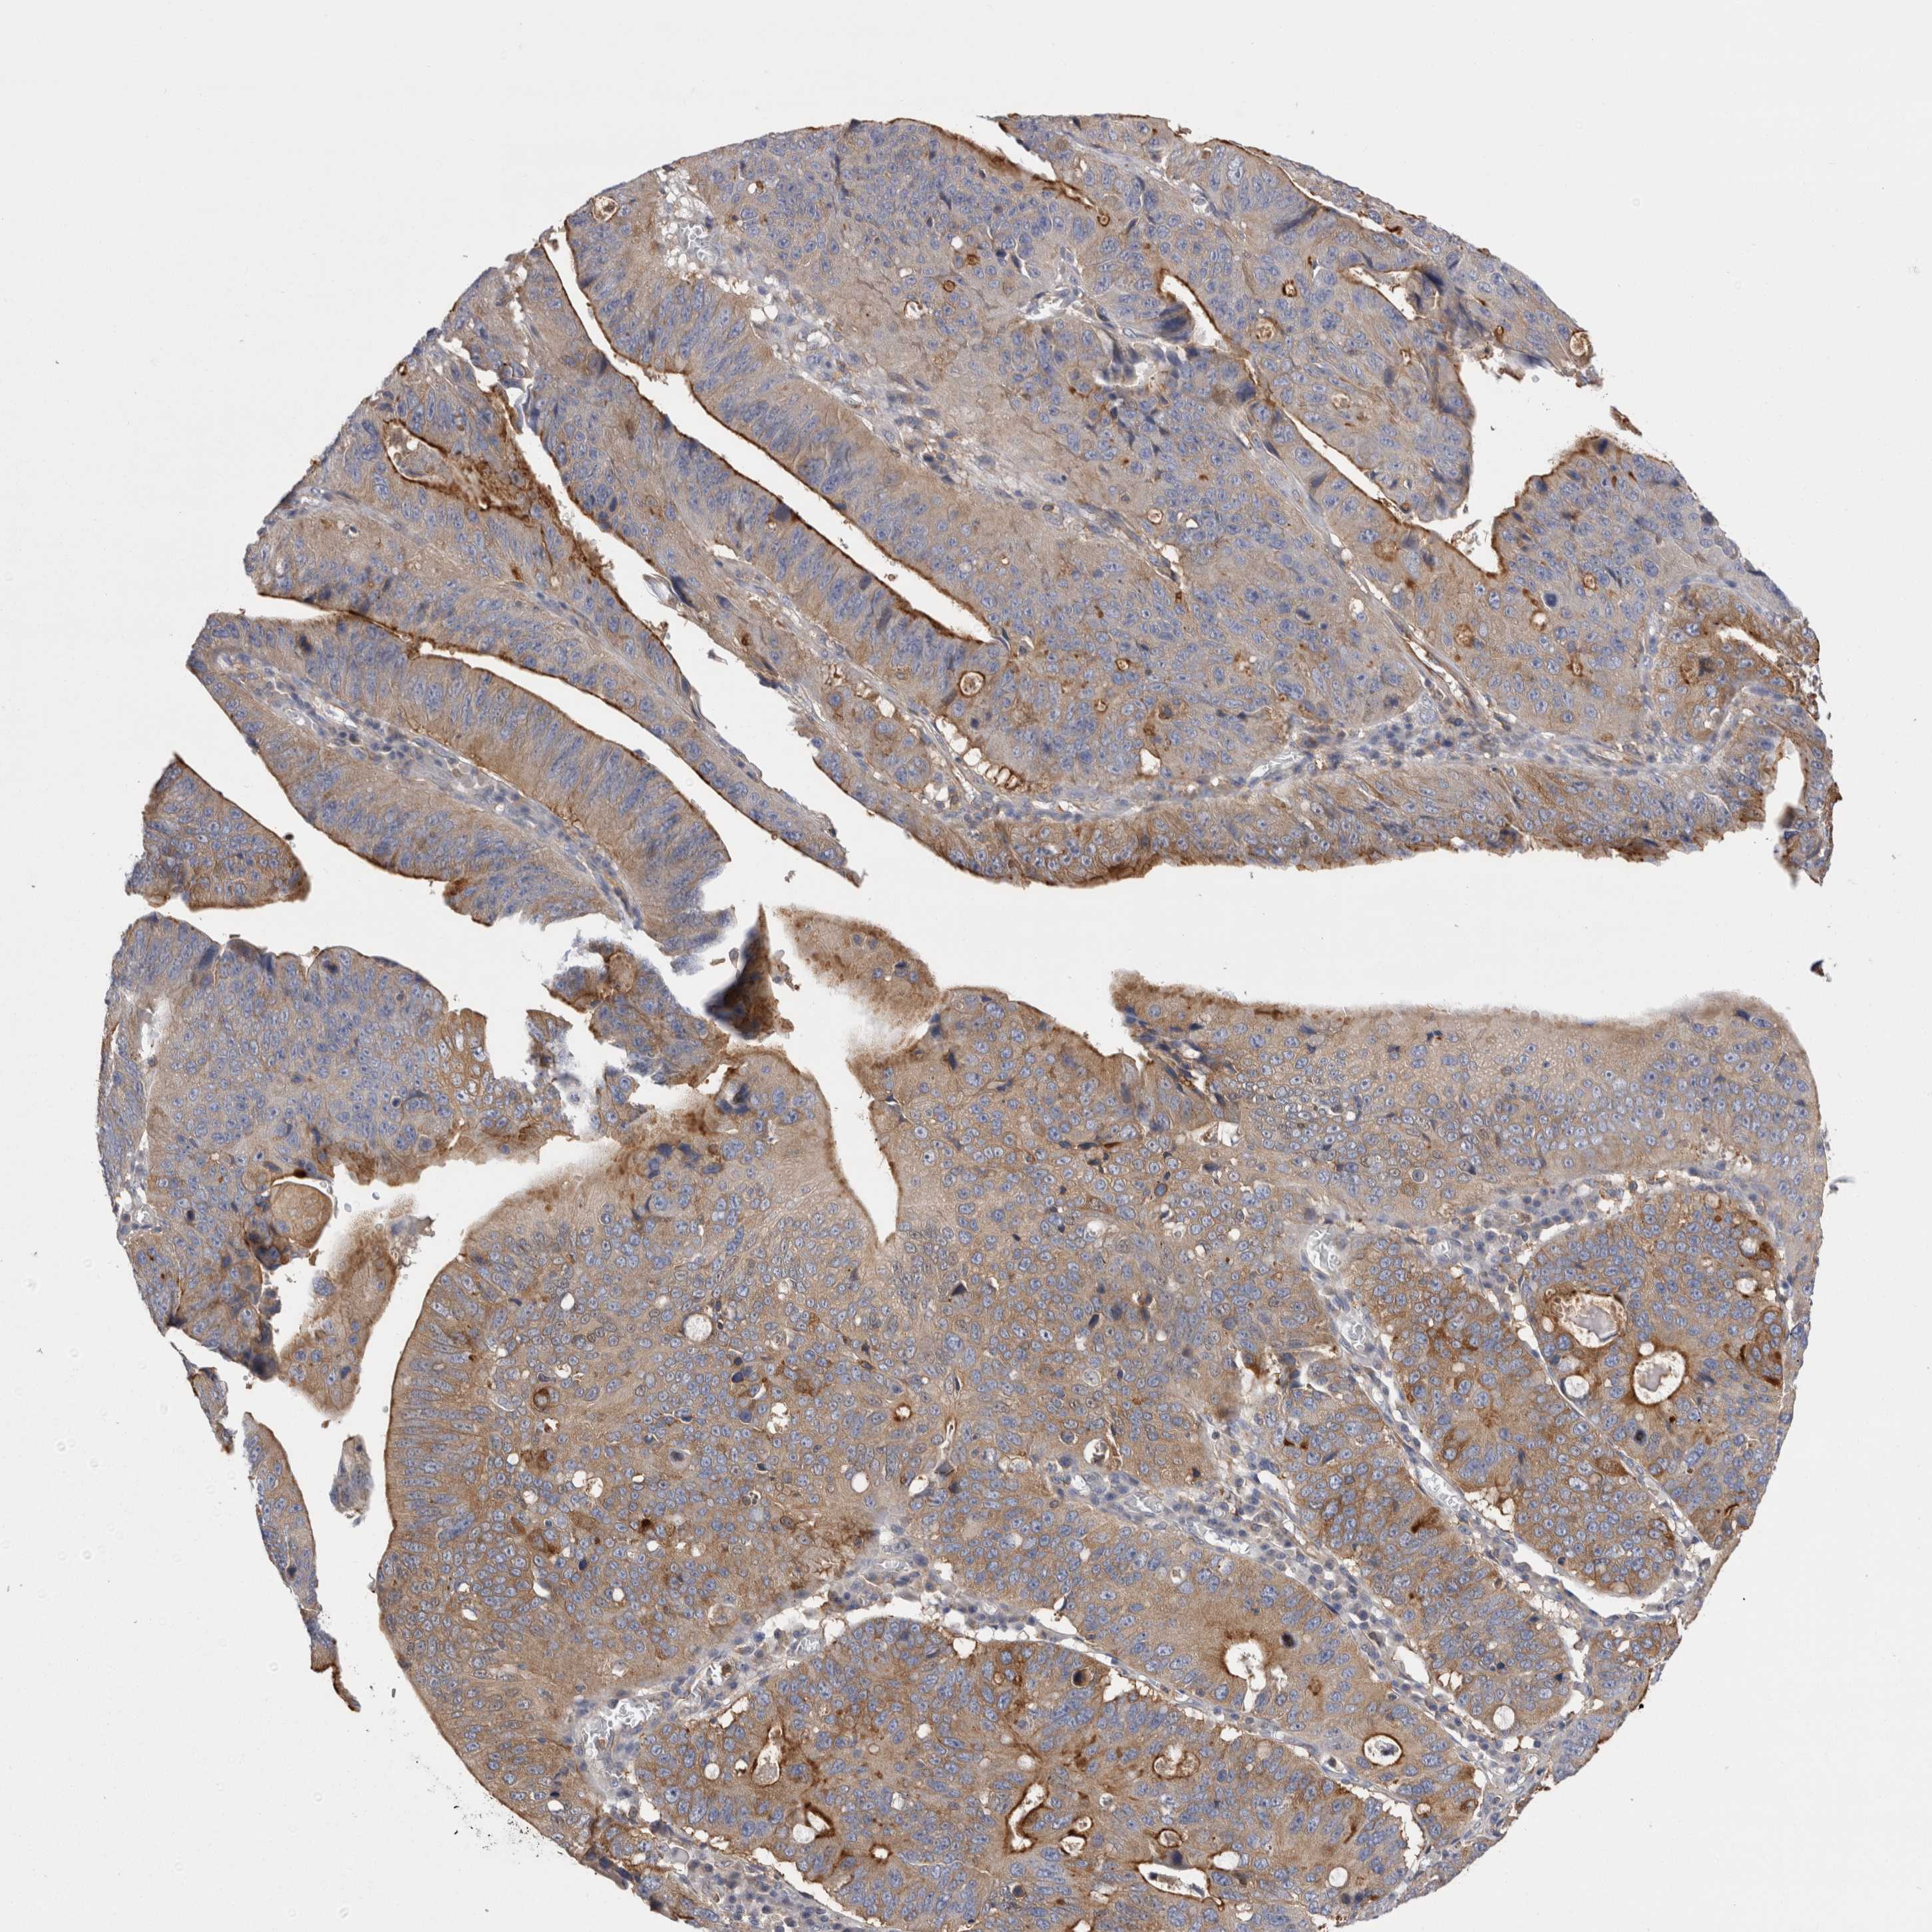

STOMACH CANCER - Protein expressioni

A mouse-over function shows sample information and annotation data. Click on an image to view it in a full screen mode. Samples can be filtered based on level of antibody staining by selecting one or several of the following categories: high, medium, low and not detected. The assay and annotation is described here.

Note that samples used for immunohistochemistry by the Human Protein Atlas do not correspond to samples in the TCGA dataset.

Antibody stainingi

Antibody staining in the annotated cell types in the current human tissue is reported as not detected, low, medium, or high, based on conventional immunohistochemistry profiling in selected tissues. This score is based on the combination of the staining intensity and fraction of stained cells.

Each image is clickable and will lead to virtual microscopy that enables deeper exploration of all samples and also displays staining intensity scores, fraction scores and subcellular localization as well as patient and tissue information for each sample.

Antibody HPA023904

Antibody HPA024010

Antibody HPA025960

Antibody CAB017037

Staining

High

Medium

Low

Not detected

Intensity

Strong

Moderate

Weak

Negative

Quantity

>75%

75%-25%

<25%

None

Location

Nuclear

Cytoplasmic/membranous

Cytoplasmic/membranous,nuclear

Adenocarcinoma, NOS